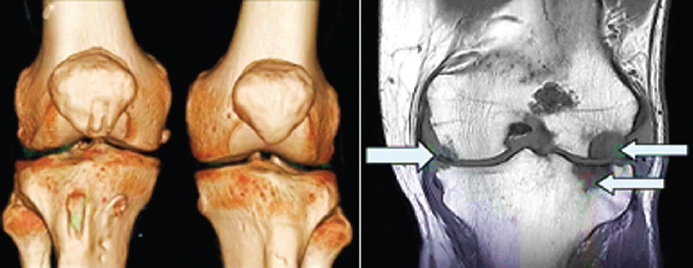

Остеоартроз (ОА) – разнородная (гетерогенная) группа заболеваний различного происхождения (этиологии) со сходными проявлением и исходом, в основе которых лежит поражение всех компонентов сустава, в первую очередь хряща, суставной оболочки, связок и других компонентов сустава (рис. 19).

Патогенез. В развитии ОА ключевую роль играют, вещества (цитокины), которые продуцируют клетки суставных тканей, а также жировая ткань (адипоциты) с избыточной массой тела. Под действием провоспалительных факторов нарушается равновесие между процессами продукции здоровых клеток и их гибелью в сторону преобладания последних, что в конечном итоге приводит к развитию заболевания (рис. 20).

Рис. 20. МРТ моделирование и фронтальный снимок коленного сустава при остеоартрозе / Fig. 20. MRI modeling and frontal image of the knee joint in osteoarthritis

Диагностика. Диагноз – остеоартроз и стадия его развития устанавливается на основании комплексной оценки состояния костной системы. Важнейшую роль в определении тактики лечения больных ОА играют методы лучевой диагностики. Помимо общих принципов ведения больных с ОА созданы обучающие программы, направленные на снижение веса при наличии ожирения, программы аэробных упражнений.